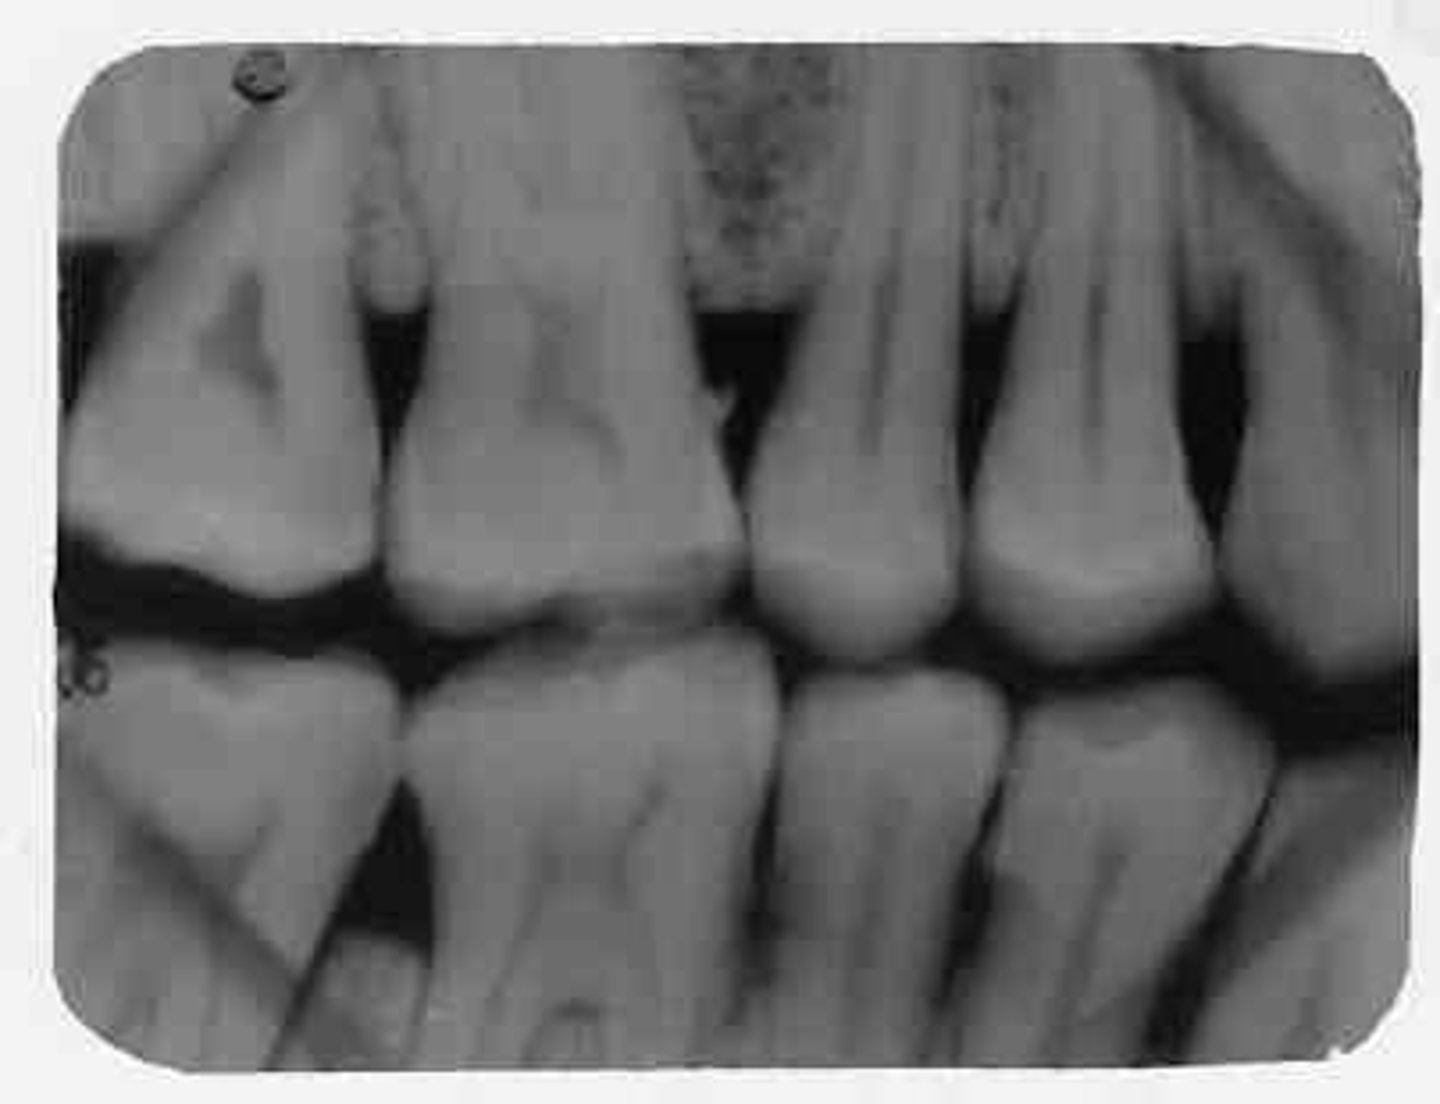

interproximal film

bitewing

shows crowns of both upper and lower teeth on same film

used to diagnose interproximal caries

sizes 0, 1, 2, or 3